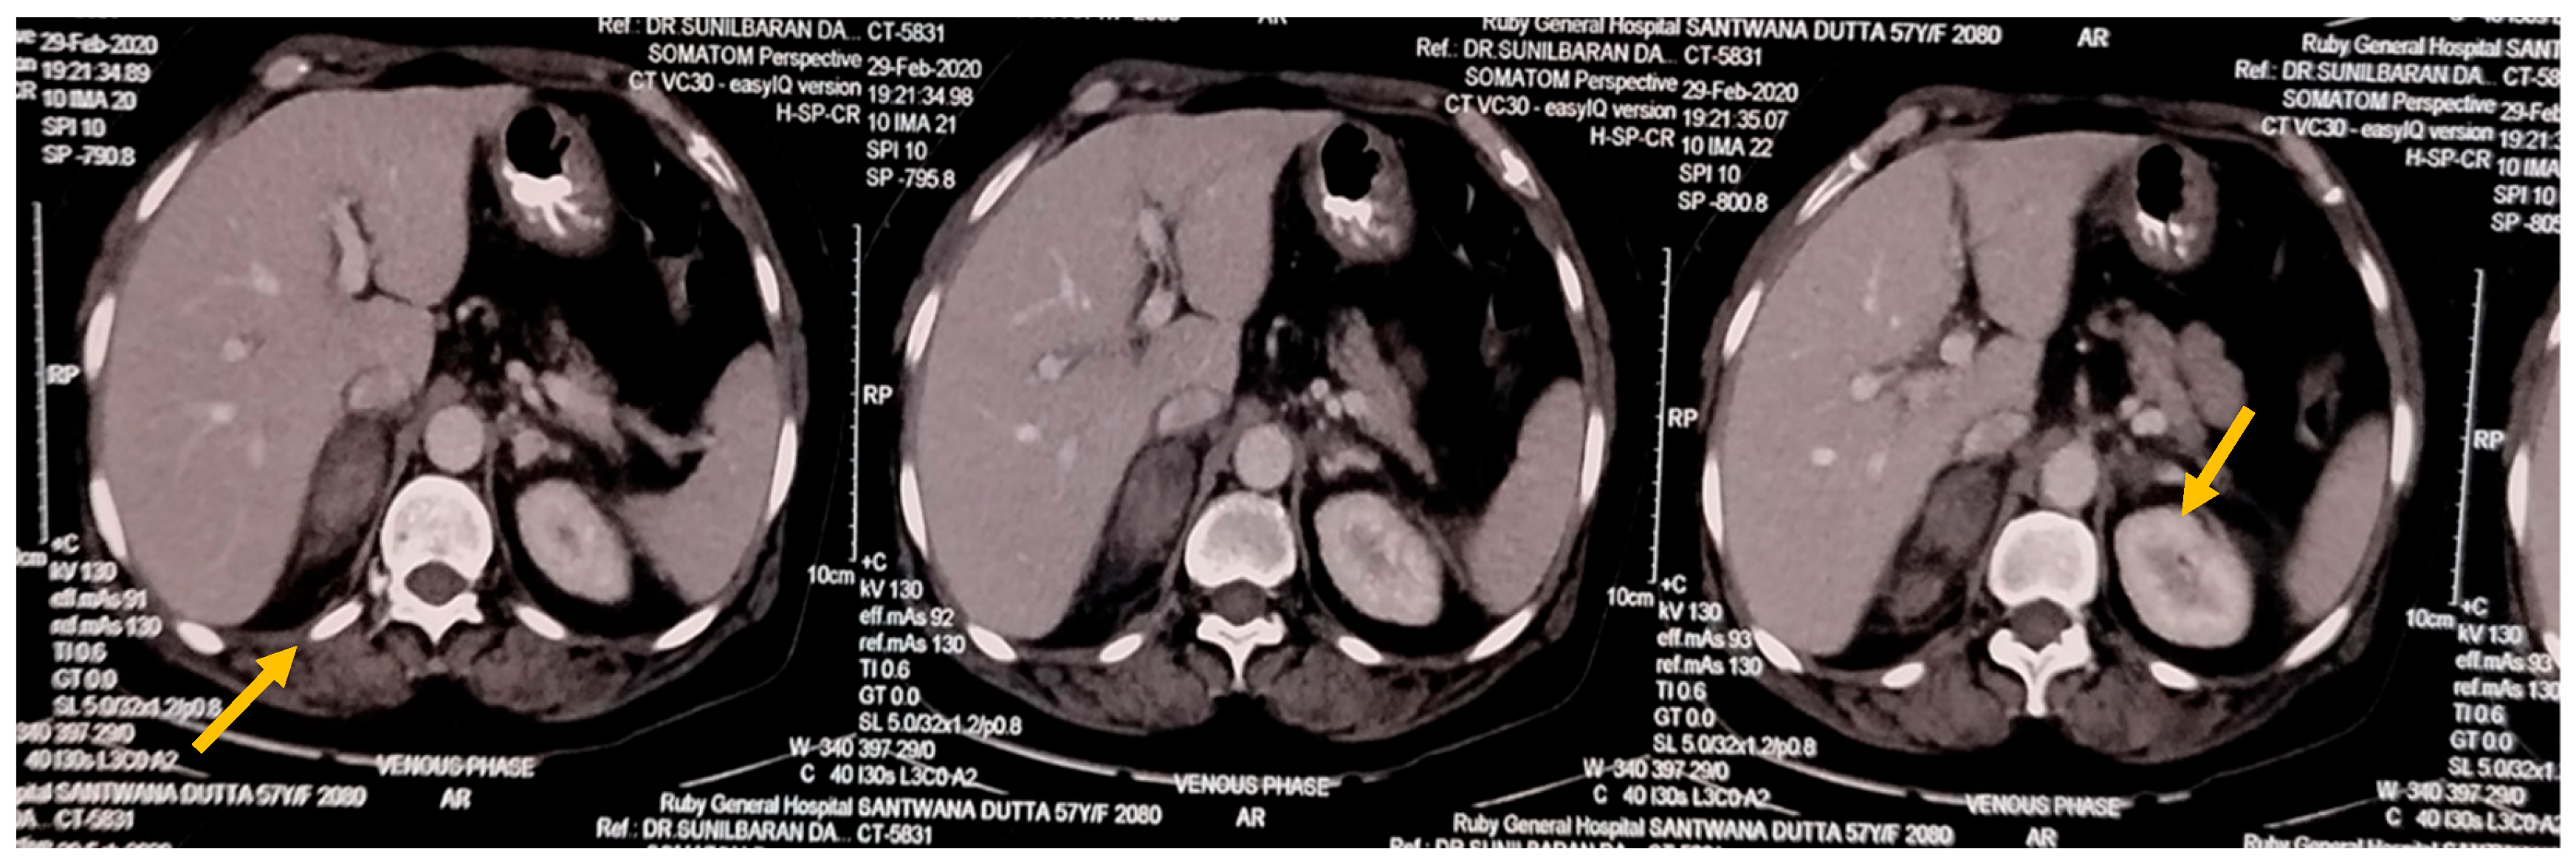

USG Whole Abdomen showed suspected Suprarenal lesion. So, CECT Abdomen was done, which showed hyperdense, non-enhancing lesion in B/L adrenal with perilesional fat stranding—likely Bilateral Adrenal Haemorrhage.

CECT Abdomen showing Adrenal Haemorrhage (marked by yellow arrows).